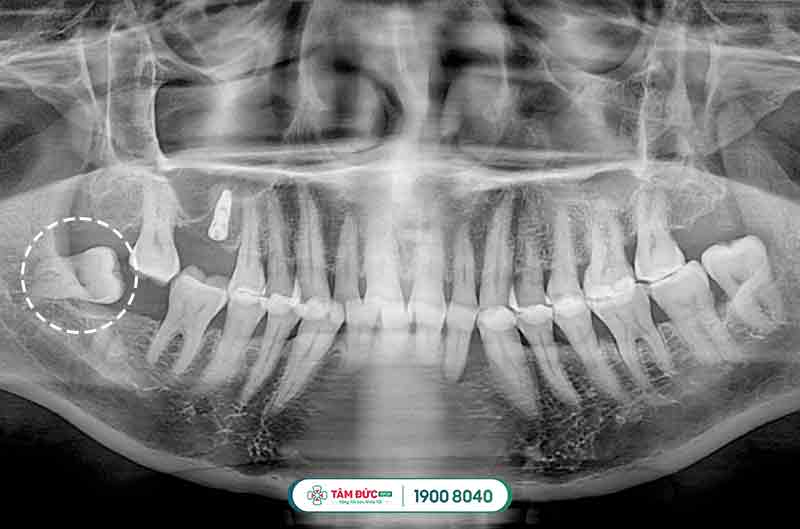

Đối với các trường hợp mọc răng khôn bị thiếu chỗ vì lúc này xương hàm đã ngừng tăng trưởng và phát triển, chịu tác động bởi quá trình ăn uống hàng ngày, khiến răng khôn bị mọc ngầm dưới nướu, mọc lệch đâm vào má, vào răng bên cạnh gây nên tình trạng đau răng khôn dữ dội, khó chịu và ảnh hưởng đến cấu trúc hàm mặt, sức khỏe răng miệng.

Răng khôn mọc lệch đâm vào răng kế cận

Răng khôn mọc ngầm thường có hiểu hiện làm nướu sưng tấy, viêm đỏ, khó há miệng. Vì xương hàm không có đủ vị trí nên nó sẽ đâm sang răng bên cạnh, nó sẽ làm chiếc răng khỏe mạnh kế bên dần bị tiêu hủy, lung lay có thể dẫn đến sâu, nặng hơn nó sẽ khiến chiếc răng này bị xô đẩy chèn ép và rụng đi gây mất răng. Răng khôn mọc lệch, ngầm thường gây ra những cơn đau răng khôn âm ỉ kéo dài trong khoản 2 tới 3 ngày.